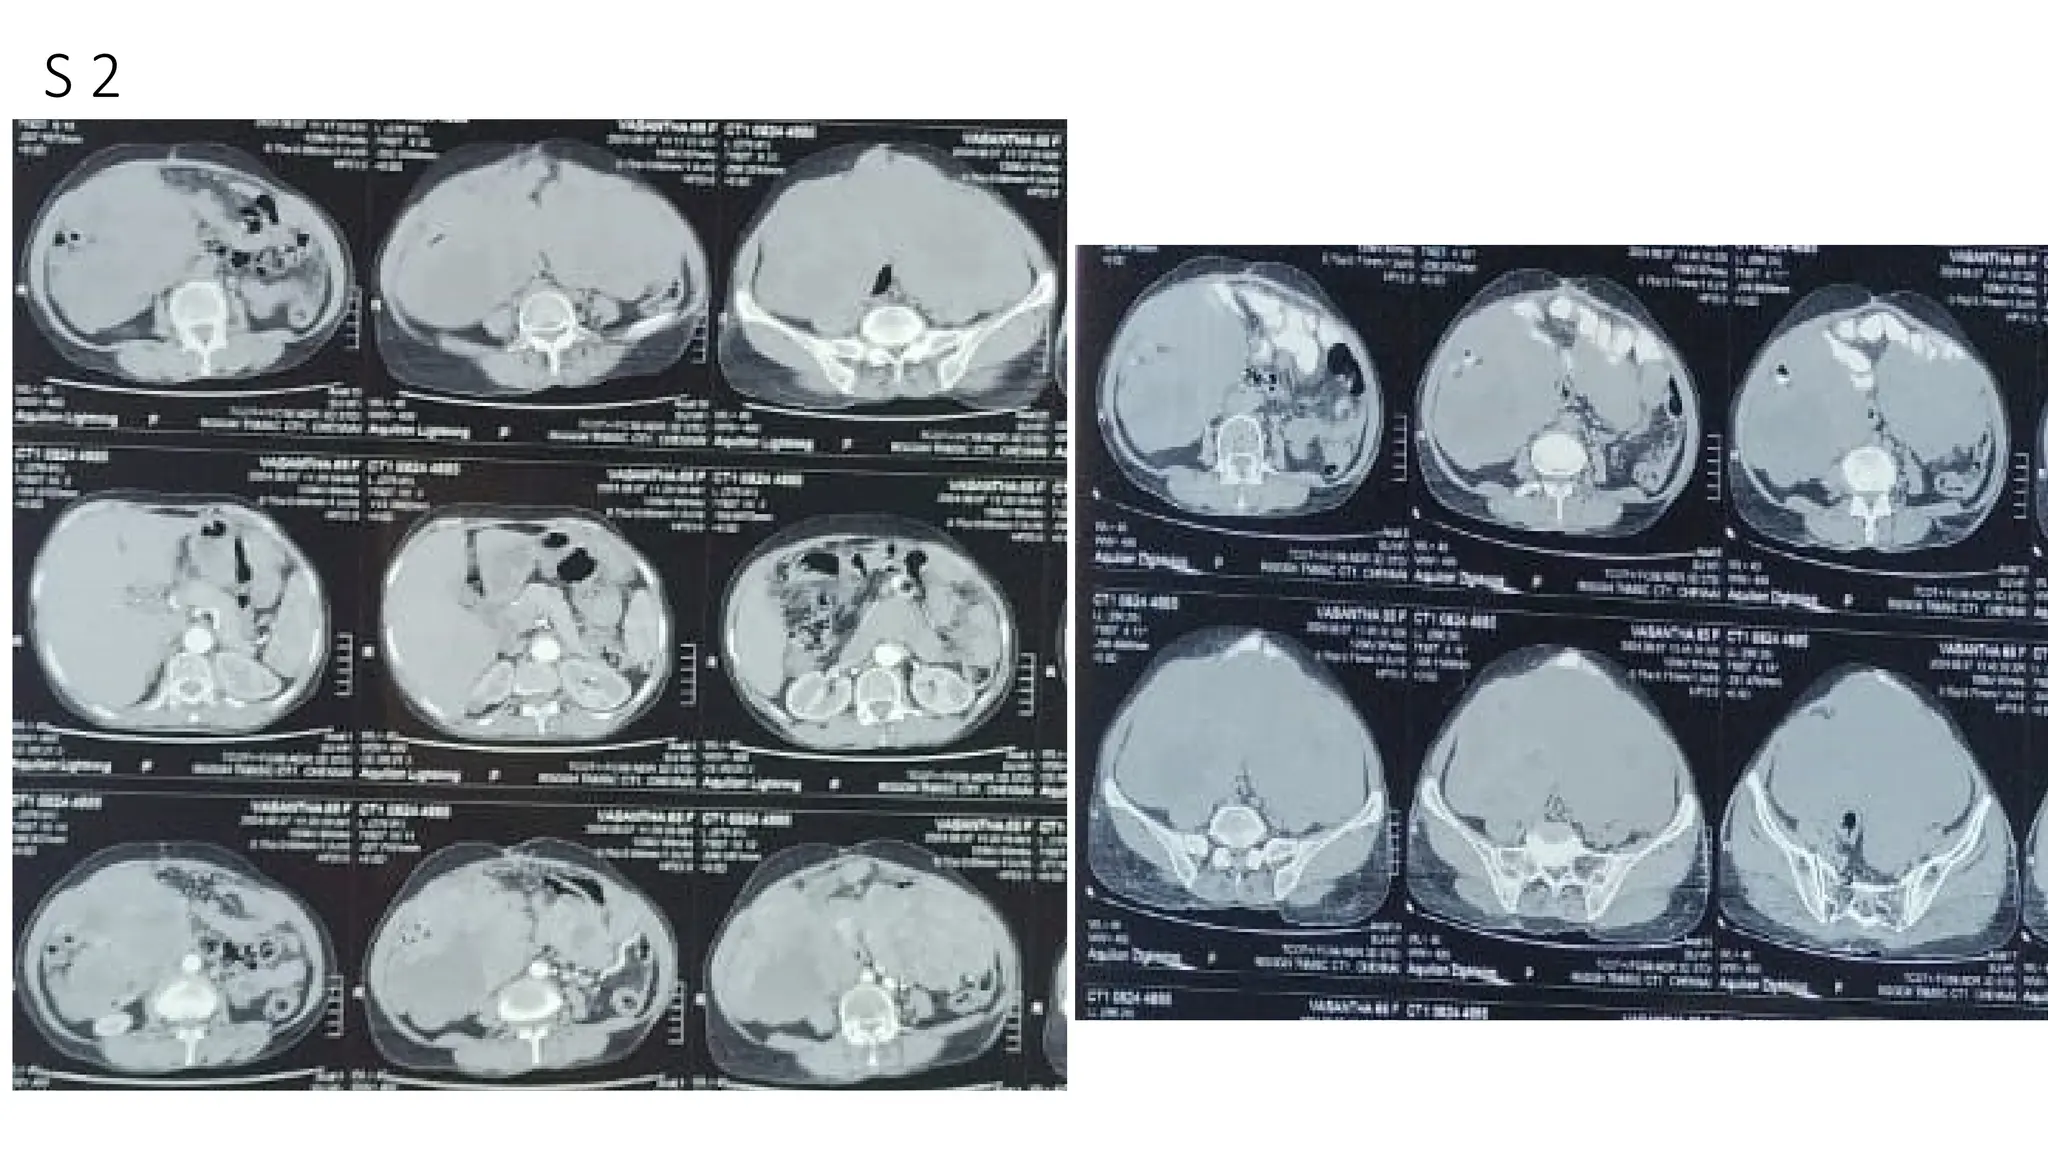

The document lists various components and classifications related to the gastro-intestinal system. It includes multiple codes and identifiers associated with different aspects of this biological system. The content appears to be a structured categorization rather than a narrative or descriptive text.